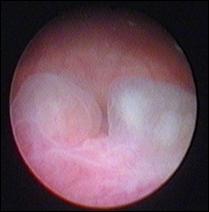

6. Diagnosticul diferential cu leziuni vezicale benigne

Aspecte cistoscopice de cistita chistica